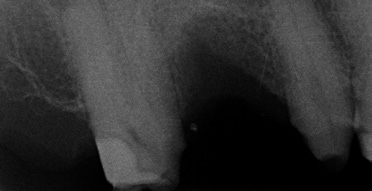

Wenn aufgrund der röntgenologischen Diagnostik klar ist, dass ich pulpennah exkavieren muss, lasse ich Carisolv einwirken und exkaviere dann mit dem PolyBur P1. Ich informiere den Patienten, dass eventuell eine Wurzelbehandlung folgen könnte, ich dies jedoch zu vermeiden versuche. Ist die Karies tatsächlich weit fortgeschritten, also tief im Dentin, kann es natürlich der Fall sein, dass ich mit PolyBur P1 die Pulpa eröffne.